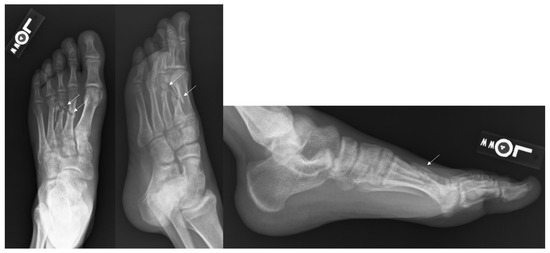

Figure 3.

Radiographs of a Metatarsal Fracture Displaced 3–4 mm. Displayed above are radiographs of a fifth metatarsal shaft fracture that is displaced between 3–4 mm. The arrows above identify the fifth metatarsal fracture.

Figure 4.

Radiographs of a Metatarsal Fracture Displaced Greater than 4 mm. Displayed above are radiographs of a fifth metatarsal shaft fracture displaced greater than 4 mm. The arrows above identify the fifth metatarsal fracture.